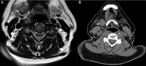

Primitive synovial sarcoma of suboccipital region in child

Ploutarchos Karydakis and others

Journal of Surgical Case Reports, Volume 2018, Issue 10, October 2018, rjy286, https://doi.org/10.1093/jscr/rjy286